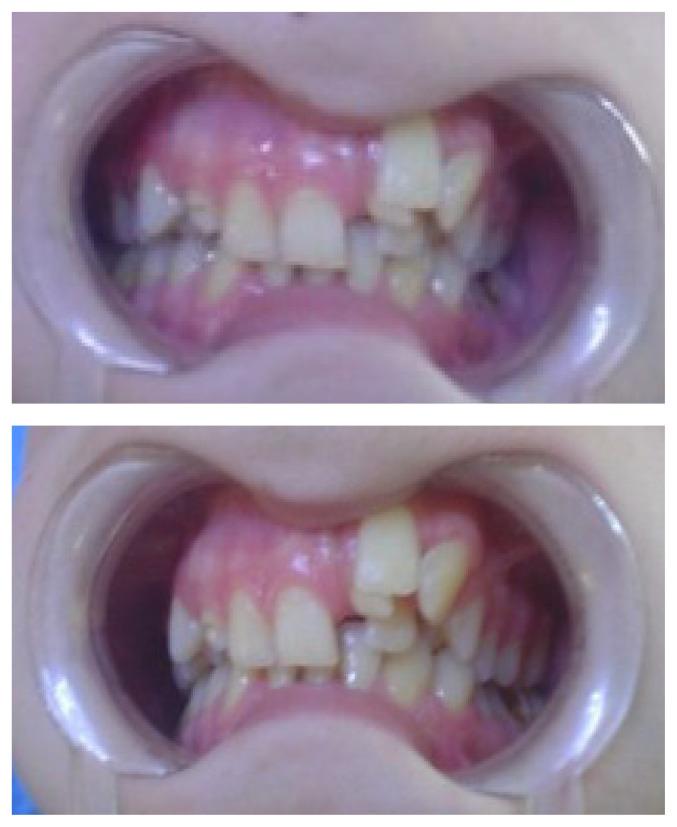

Tooth number abnormalities may occur under the influence of genetic or environmental factors which intervene in the tooth formation stages (induction and proliferation), most commonly the permanent dentition being affected. The result is the appearance of dental anomalies with numerical deficiency (hypodontia, anodontia), or with dental excess (hyperodontia, over-teeth). In this paper we report a case of a 15-year-old boy with associated abnormalities of permanent dentition: mesiodens and palatal impacted cuspid at the maxillary dental arch and incisor anodontia at the mandibular dental arch. Orthodontic treatment aimed at resolving maxillary dental crowding, obtaining dental alignment, a stable and functional occlusal relationship and a satisfactory smile for the patient.

牙齿数目异常可能在影响牙齿形成阶段(诱导和增殖)的遗传或环境因素作用下发生,最常受影响的是恒牙列。结果是出现牙齿数目不足(缺牙症、无牙症)或牙齿过多(多生牙、额外牙)的牙齿异常情况。在本文中,我们报告了一例15岁男孩伴有恒牙列相关异常的病例:上颌牙弓有正中多生牙和腭侧埋伏尖牙,下颌牙弓有切牙无牙症。正畸治疗旨在解决上颌牙列拥挤问题,实现牙齿排列整齐、稳定且功能良好的咬合关系,并为患者打造令人满意的笑容。